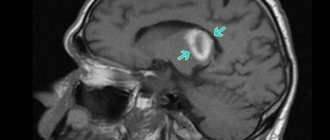

Когда пациент с инсультом левого полушария доставлен в больницу, врач проводит его полный осмотр, который также включает инструментальную диагностику. Она позволяет определить масштаб кровоизлияния, локализировать очаг повреждения и определить форму инсульта. Во время аппаратной диагностики проводят:

1. МРТ головного мозга.

2. Компьютерную томографию.